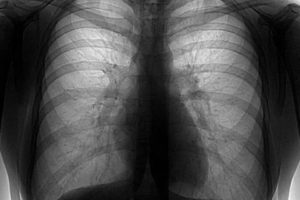

Флюорография лёгких фото

Пневмония – воспаление легких, которое может возникать в любом возрасте, но чаще у детей. Она разделяется по этиологии (вызвавшим ее возбудителям), степени тяжести, локализации воспаления (очаговая, крупозная, сегментарная, прикорневая и пр.). Фото снимков при пневмонии можно увидеть ниже.

Определить пневмонию можно с помощью данных аускультации и клиники; анализа крови (картина лейкоцитоза), инструментального исследования — флюорографии (ФЛГ) или рентгена легких – снимок легких при пневмонии.

На снимке легких при пневмонии получается, что негатив окрашивает самые плотные части в белый цвет, и кости в т.ч., пустые части – делает черными, органы – дают серые цвета разных оттенков.

Пневмония или воспаление хорошо визуализируется на рентгене и выглядит как инфильтративная тень на фоне усиления лёгочного рисунка, вокруг очага часто бывают просветления — локальная компенсаторная эмфизема.

Рентгенологическая диагностика — «золотой стандарт» в диагностике заболеваний органов дыхания. Благодаря воздушности ткани лёгких рентгенография хорошо визуализирует воспалительные изменения, обструкцию бронхов и разрастание патологического субстрата онкологии или туберкуломы. Простота и дешевизна методики позволяет использовать её для контроля динамики в течение терапии.